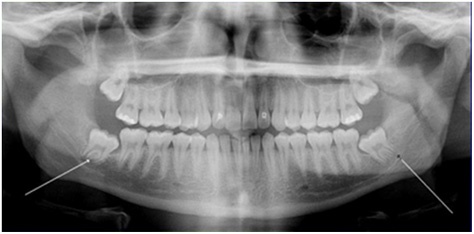

Our mouth is one crowded place!! It can hold a total of 28 teeth with 32 teeth vying for those 28 spots!! Wisdom teeth aren’t just for show. They play a vital part in limiting the wear on the rest of your teeth. Where are wisdom teeth? They are located behind your molars in the back of your mouth. Anthropologists believe that wisdom teeth were developed in order to chew “rough foods,” such as nuts, meat and leaves. We get many patients wondering why these important teeth need to be removed? Crowding is the simple answer.

Crowding causes severe pain and will ultimately degrade the teeth surrounding your wisdom teeth. We get lots of patients initially rejecting the idea of getting their wisdom teeth extracted but come back to us in a matter of months to get them removed as a result of the extensive pain of this concept. Major symptoms of wisdom teeth crowding is pain in the back of your mouth as well as a great deal of swelling in the same area. If this pain is increasingly getting stronger do not hesitate to call us immediately! If left untreated, severe oral infections can cause a variety of outcomes such as bad breath to even tumors! Getting these attended and checked out by marketplace Dental Centre, you are ensuring you are getting the upmost and professional cleaning anywhere in Georgetown!!